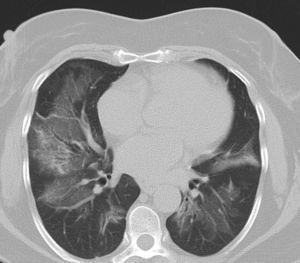

Pulmonary manifestations can be an extraglandular complication, with reported prevalence varying widely (9–75%), depending on the methods of detection and patient selection. Lung involvement (symptoms and either pulmonary function testing or radiographic abnormalities) can occur in 10–20% of patients.2 Image techniques, such as chest radiographs and high resolution computerized tomography (HRCT), are the most useful tools to detect lung involvement. A plain chest X-ray has a low sensitivity to detect early lung involvement. Studies that systematically perform HRCTs, even in asymptomatic patients, report higher rates of pulmonary abnormalities compared with studies based on clinical symptoms.3 HRCT may identify ground-glass attenuation, thin-walled cysts, honeycombing, reticular pattern, small nodules and enlarged mediastinal lymph nodes. Several histopathologic patterns have been described in PSS, including nonspecific interstitial pneumonia (NSIP), usual interstitial pneumonia (UIP), organizing pneumonia (OP) and lymphocytic interstitial pneumonia (LIP). Most of these patterns are known as diffuse interstitial lung disease (ILD). LIP has a typical radiographic appearance in ground glass opacities with thin-walled cysts, and the presence of these cysts on HRCT scan should raise clinical suspicion for PSS with ILD.4,5

NSIP is the most commonly observed histopathological pattern in connective tissue diseases with ILD, including PSS. In patients with PSS and ILD, HRCT and histopathological findings are well correlated6 and a lung biopsy is usually not recommended. However, radiographic features suggestive of lymphoma (consolidation, large nodules or pleural effusions) require thorough investigation7 (Figs. 1–3).